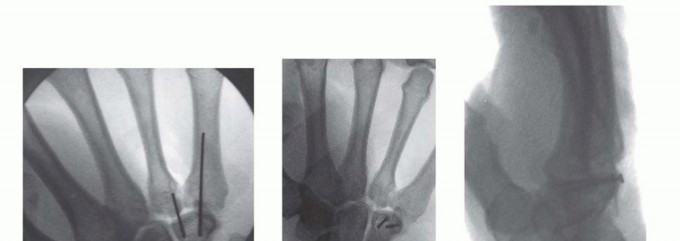

Once exposed, the fracture hematoma is meticulously debrided. In the setting of a scaphocapitate syndrome, the surgeon may encounter the daunting scenario of a capitate head that has rotated 180 degrees. Reduction requires delicate manipulation, often utilizing a dental pick or a small periosteal elevator as a joystick, combined with longitudinal traction. Extreme care must be taken to avoid further stripping of the tenuous palmar soft tissue attachments, which harbor the critical remaining blood supply. Once anatomic reduction is achieved, provisional fixation is secured with multiple 0.045-inch Kirschner wires.

Definitive fixation is optimally achieved using headless compression screws. For capitate neck fractures, an antegrade trajectory (from the dorsal proximal pole directed distally into the body) or a retrograde trajectory (from the dorsal body directed proximally into the head) can be utilized, depending on fracture morphology and fragment size. The screw must be entirely buried beneath the articular cartilage to prevent devastating midcarpal impingement. Intraoperative fluoroscopy is utilized continuously to confirm anatomic reduction, verify screw length, and ensure no hardware penetrates the articular surfaces. If comminution is severe, supplemental K-wire fixation or even a miniature dorsal spanning plate may be required.

For ORIF, the fracture site is exposed by carefully elevating the hypothenar musculature originating from the hook. The fracture is reduced and provisionally held with a K-wire. A cannulated headless compression screw (typically 2.0mm or 2.4mm) is then advanced over a guidewire from the tip of the hook down into the body of the hamate. Fluoroscopy is critical to ensure the screw does not penetrate the articular surface of the hamate body or impinge upon the CMC joints.

Clinical & Radiographic Imaging Archive